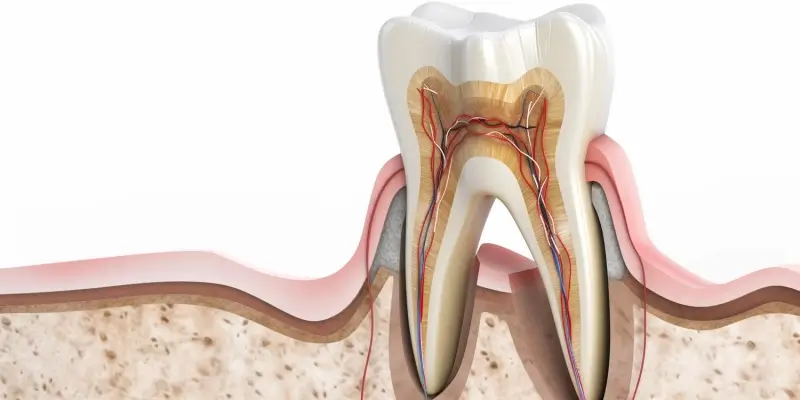

Głównym zadaniem stomatologa jest profilaktyka, diagnostyka i leczenie chorób zębów, dziąseł, przyzębia oraz jamy ustnej. Obejmuje to szeroki zakres procedur, od prostych zabiegów higienizacyjnych, przez wypełnianie ubytków, leczenie kanałowe, ekstrakcje zębów, aż po bardziej skomplikowane zabiegi chirurgiczne i protetyczne. Stomatolog musi posiadać dogłębną wiedzę z zakresu anatomii, fizjologii, patologii, farmakologii i radiologii, aby móc trafnie diagnozować i skutecznie leczyć pacjentów.

Kluczowym elementem pracy stomatologa jest wykonywanie zabiegów leczniczych. Są to między innymi wypełnianie ubytków próchnicowych różnymi materiałami, leczenie endodontyczne (kanałowe) zainfekowanych zębów, usuwanie zębów, które nie nadają się do leczenia, a także przeprowadzanie zabiegów chirurgii stomatologicznej, jak np. usuwanie ósemek, resekcje wierzchołków korzeni, czy też przygotowanie pacjenta do zabiegów implantologicznych. Poza leczeniem, stomatolog zajmuje się także protetyką, czyli odtwarzaniem braków zębowych za pomocą koron, mostów czy protez.

Kolejnym przełomem jest zastosowanie tomografii komputerowej stożkowej (CBCT), która umożliwia uzyskanie trójwymiarowych obrazów struktur jamy ustnej i szczęki. Pozwala to na dokładną analizę kości, korzeni zębów i nerwów, co jest nieocenione w planowaniu skomplikowanych zabiegów chirurgicznych, implantologicznych czy ortodontycznych. Mikroskopy stomatologiczne to kolejne narzędzie, które znacząco zwiększa precyzję pracy stomatologa, szczególnie w leczeniu kanałowym. Pozwalają one na powiększenie pola zabiegowego nawet kilkukrotnie, co umożliwia dostrzeżenie najdrobniejszych szczegółów i dokładne opracowanie systemu korzeniowego.